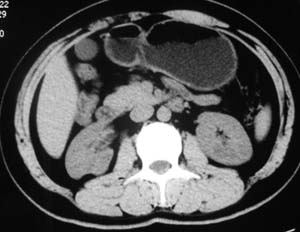

以下是引用子期在2010-3-19 20:47:00的发言:[br]血管畸形的ct增强应该有明显强化,本例并不相符合。本例双肾局部的略低密度影,累及肾盂,局部皮质明显变薄、内陷,增强扫描有轻度的强化,应考虑为炎性病变,患者为年轻男性,累及双肾的感染以结核较常见,可以没有明显的临床症状,尿中有时候也并不能查出什么;肾脓肿常有明显感染中毒症状,本例不符,另外一般的肾盂肾炎或肾小球肾炎通过小便就可确诊,其它还不能排除的是黄色肉芽肿性肾盂肾炎,然而单凭ct一般也很难鉴别。